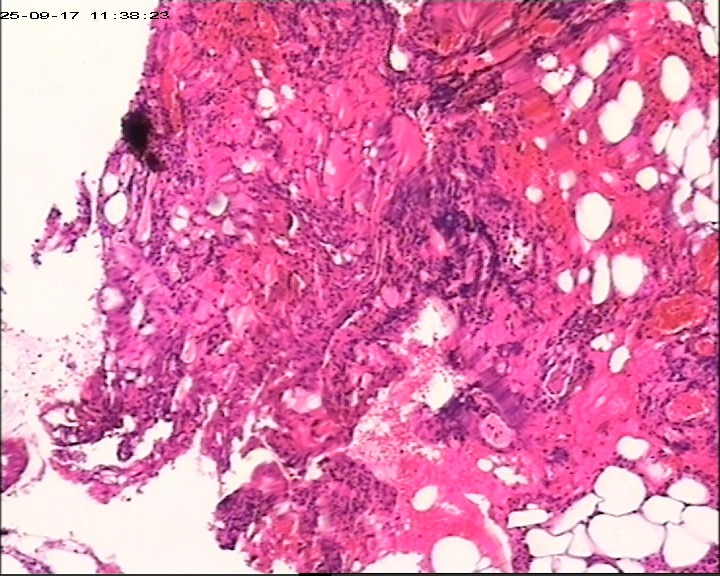

臀部组织,请帮忙看看,谢谢

性别

男

年龄

20岁

临床诊断

一般病史

藏毛窦或囊肿切开术

标本名称

臀部

大体所见

灰白灰黄碎组织一堆,大小为6.5*4*1cm。

图2

描述诊断炎性病变